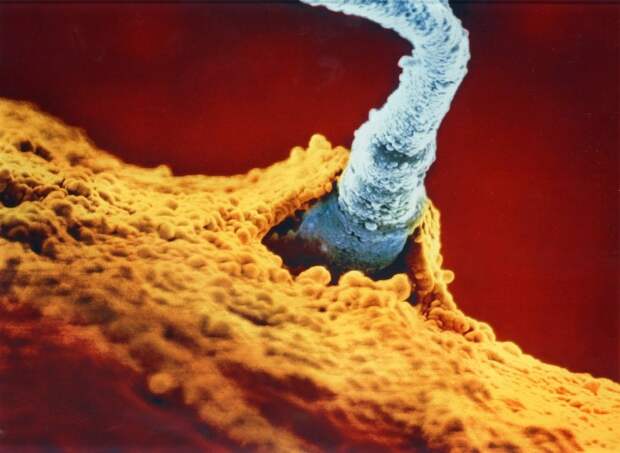

Головка сперматозоида в разрезе, именно в ней заложен весь генетический материал, способствующий правильному дальнейшему развитию.  Зародыш прочно прикрепился к стенке матки.

Зародыш прочно прикрепился к стенке матки.  На 22-ой день развития начинаются самые настоящие чудеса (серым отмечен будущий мозг младенца).